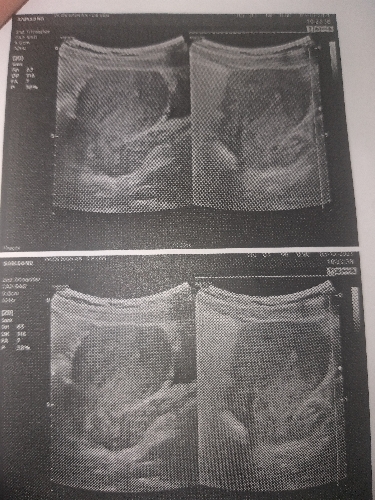

Chào bác sĩ ! Ngày( 9/9) e có quyết định nhập viện lấy thai ra vì thai đã bị lưu 7 tuần và xuất viện 2 ngày sau đó .e tái khám sau 1 tuần thì bác sĩ nói là e còn ứ dịch và kiêu em về nhà uống canh bồ ngót cho ra hết hẹn 2 tuần sau tái khám. Sau 2 tuần ngày( 3/10 )e tái khám và bác sĩ nói đã hết ứ dịch và sạch rồi ạ. Nhưng mấy hôm nay e thường bị ra ít máu nâu có ngày có ngày không ,vậy cho e hỏi tình trạng của em là bị sao ạ?